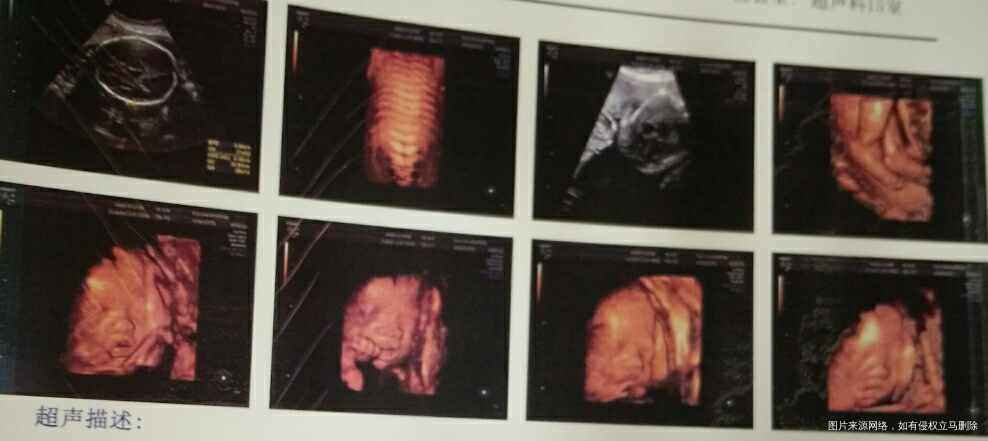

一眨眼,孕期过了一半多了,妈妈该给宝宝照照片啦。那几天跟你爸爸一直讨论你是男生还是女生?是胖娃娃还是瘦小孩?是调皮捣蛋鬼还是文静好baby……

带着那么多的疑问,妈妈去做了三维彩超,阿姨说你是个小调皮虫呢,跟阿姨玩躲猫猫,一下子害羞遮起半张脸,一下又大展拳脚,费了半天劲终于搞定啦。把照片发给爷爷看时,爷爷说你肯定是个小帅哥,脚丫子那么大个[偷笑]